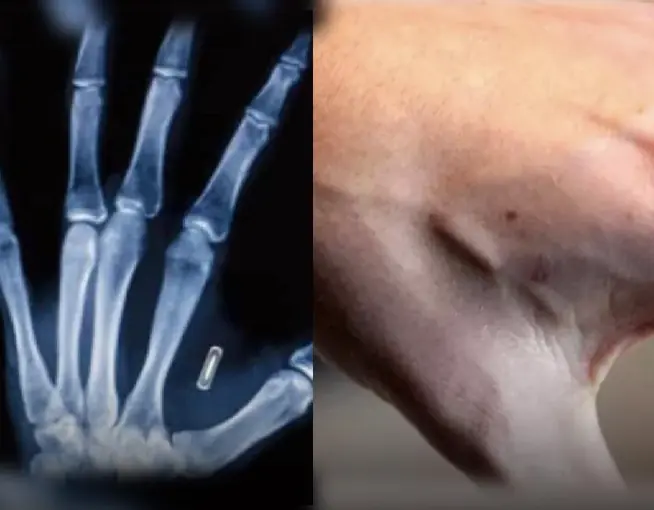

ผู้คนนับพันกำลังฝังไมโครชิปใต้ผิวหนังเพื่อใช้แทนกุญแจ บัตร และเอกสารส่วนตัว